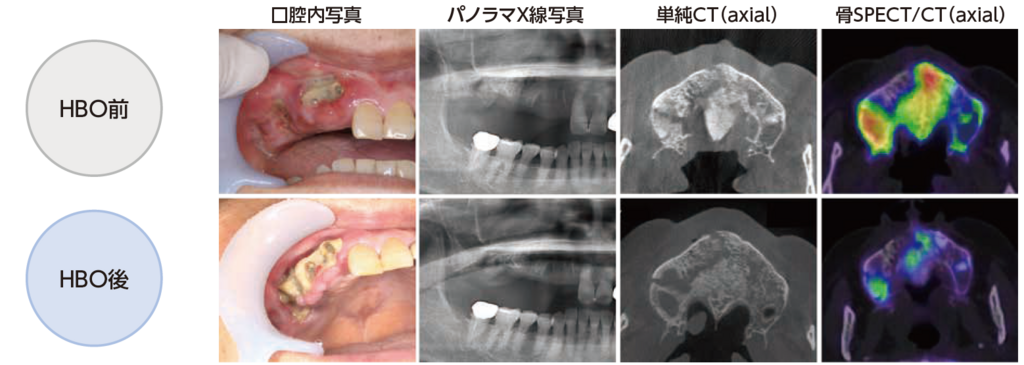

HBO15回施行後:口腔内写真およびパノラマX線写真(右側のみ掲載)

腐骨は露出し、周囲歯肉の発赤・腫脹は軽減、腐骨周囲からの排膿量はかなり減少し、自発痛は消失した。パノラマX線写真では、骨硬化像が薄くなっているように見えるが、それほど大きな変化は認めない。

HBO15回施行後:単純CT画像&骨SPECT/CT画像

単純CT画像:腐骨分離が明瞭となり、上顎洞底には薄い骨の境界(▼)が認められる。

骨SPECT/CT画像:分離した腐骨周囲の骨に淡いRI集積を認めるのみであった。

HBO15回施行前後:各所見の比較

単純CT画像は、腐骨の分離状態を確認することはできるが、骨SPECT/CT画像では、腐骨の範囲のみならず炎症波及の程度が確認できることから、HBOの治療効果をより視覚的に判定することができる。